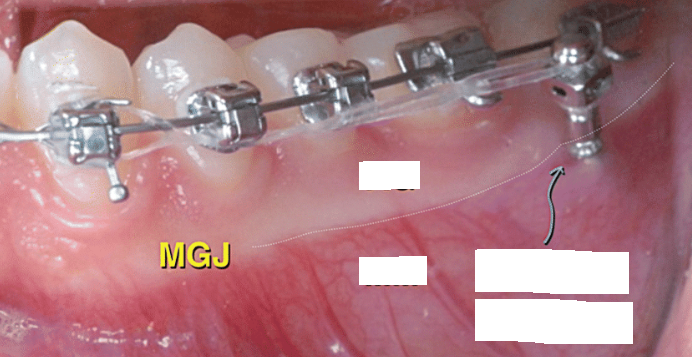

mucogingival junction

clinically visible boundary where the pink attached gingiva meets the red, shiny alveolar mucosa

clinically visible (demarcations)

free gingival groove

A shallow linear depression that separates free and attached gingiva

rarely visible to the naked eye (demarcations)

common mucogingival deformity

gingival recession

Miller gingival recession classification

Class I

marginal tissue that does not extend to MGJ

Class II

marginal tissue recession that extends to or beyond MGJ with no periodontal loss in the interdental area

Class III

marginal tissue recession that extends to or beyond MGJ with interdental bone or soft-tissue loss and/or mal-the positioning of teeth

Class IV

marginal tissue recession that extends beyond MGJ with severe loss of interdental bone to level corresponding to most apical extent of marginal tissue recession